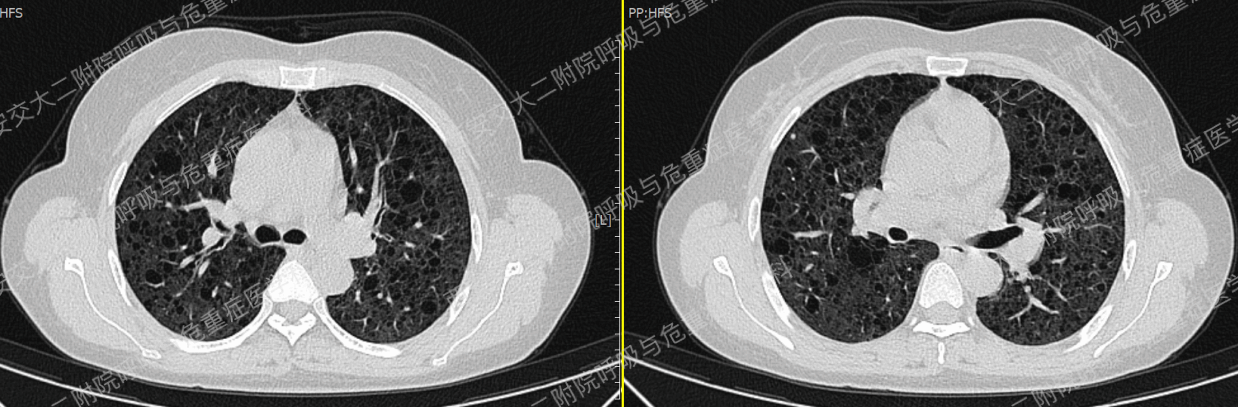

以下2例不同患者的胸部影像改变,又分别考虑什么疾病呢?